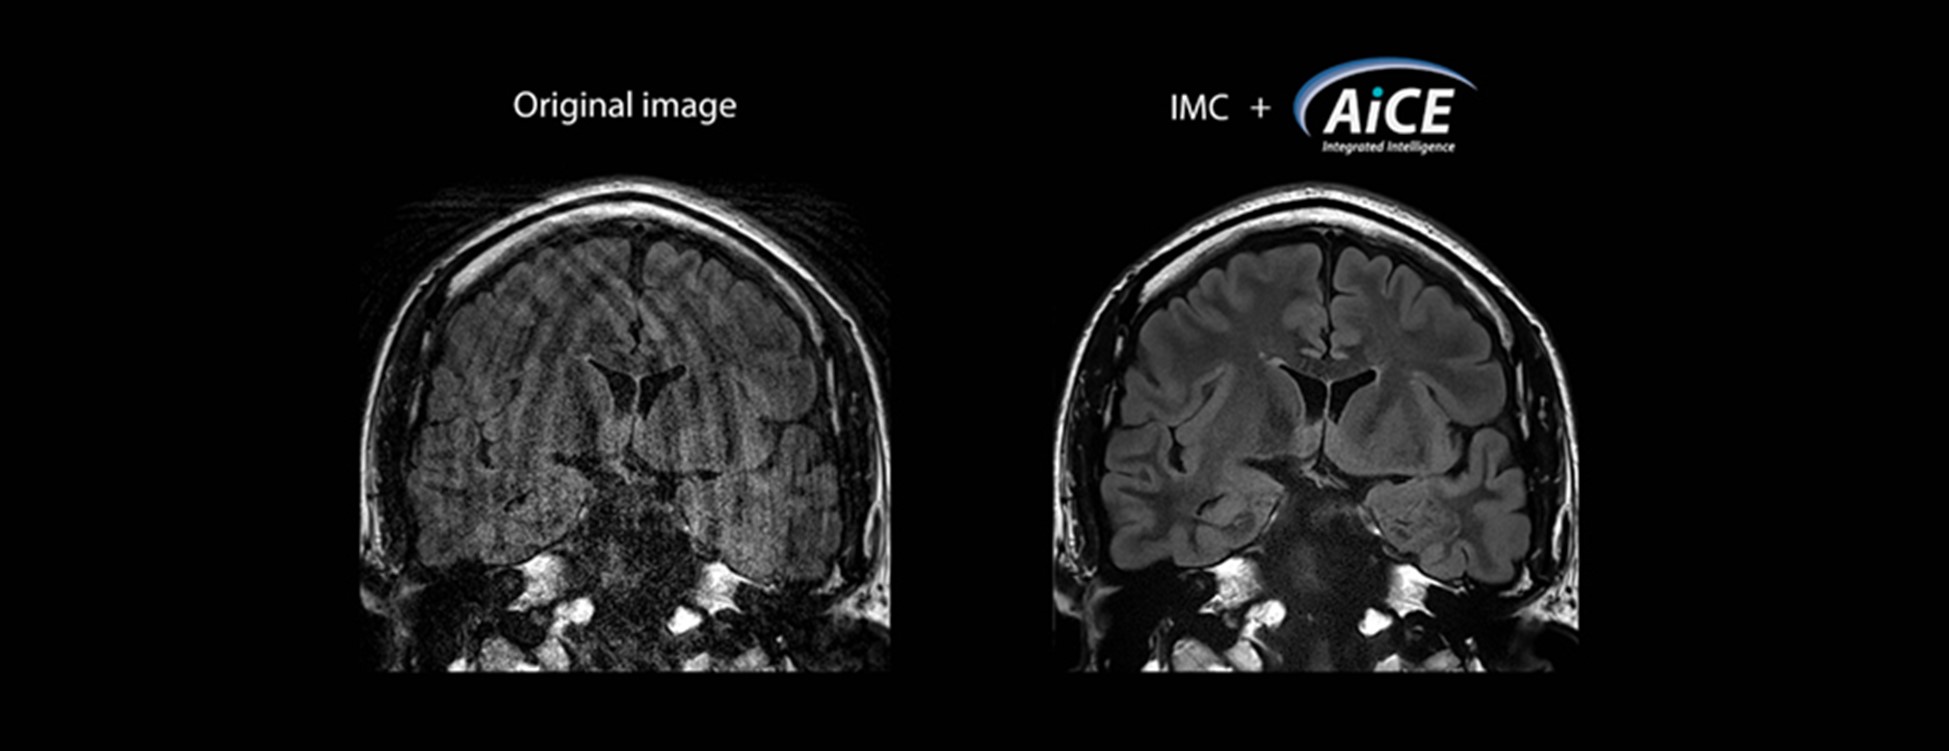

IMC також можна використовувати в поєднанні з нейронною мережею глибокого навчання Advanced intelligent Clear-IQ Engine (AiCE). Як показано на рис. 2, завдяки використанню IMC у поєднанні з AiCE, покращення SNR і придушення руху дають змогу надавати більш цінні зображення, і очікується, що такі нові технології покращать якість обстеження та майбутню діагностику у світі радіології після COVID-19.

Рис. 2: Приклад зображення до якого застосовано IMC і AiCE. У порівнянні з оригінальним зображенням (зліва), оброблене зображення (справа) має кращу якість зображення з точки зору SNR і придушення артефактів руху.